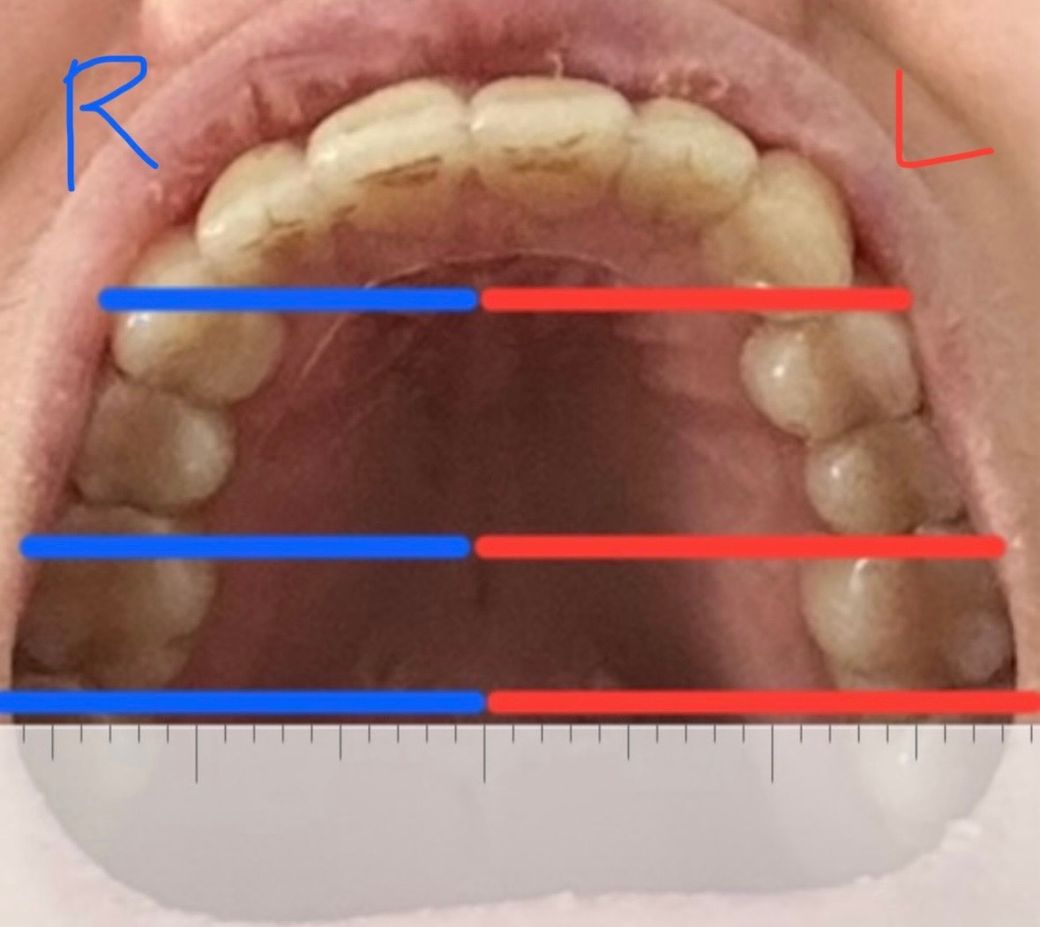

치아교정 치아중심선 안맞고 양쪽 넓이 달라도 괜찮은가요?

악궁 넓이가 양쪽 다르고 치아들이 왼쪽으로 쏠려있는 느낌에 얼굴이 휘게 틀어진 U자로 교정된거같아요.

치아교정 잘못된건가요? 보시기에 어떠신지 간단하게라도 말해주시면 정말 감사하겠습니다.